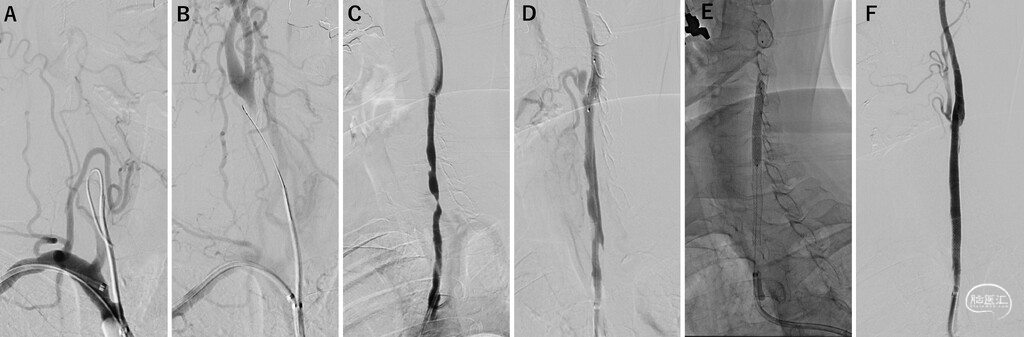

FIG. 2. Antegrade recanalization attempt for right CCA chronic occlusion and carotid artery stent placement for left CCA stenosis. A: A balloon-guiding catheter was placed proximal to the vertebral artery to sandwich the CCA origin. A Guidepost was inserted into the occluded CCA using a RADIFOCUS guidewire. B: The SL-10 microcatheter and CHIKAI 14 guidewire entered the false lumen of the CCA. C: Left CCA angiogram showing high-grade stenosis of the left CCA. D: After balloon angioplasty and deployment of a SpiderFX device in the internal carotid artery, angiography showed dissection of the CCA. E: With the balloon-guiding catheter expanded in the CCA for proximal protection, three stents were deployed in a connected fashion from the ICA to the CCA, followed by balloon angioplasty. F: Left CCA angiogram showing good expansion.